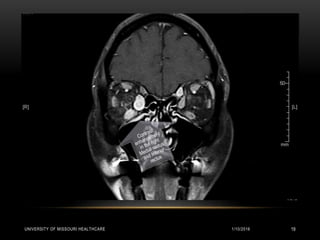

RADIOLOGY

MRI of the Brain:

• Bilateral symmetrical calcification in bilateral basal ganglia, thalami, cerebellar dentate

nuclei suggestive of Fahr’s disease.

• Right sided proptosis with enlargement and increased enhancement of the inferior rectus

and medial rectus. Increased enhancement of the left superior oblique muscle. Primary

consideration is Thyroid orbitopathy / Pseudotumor / Myositis.